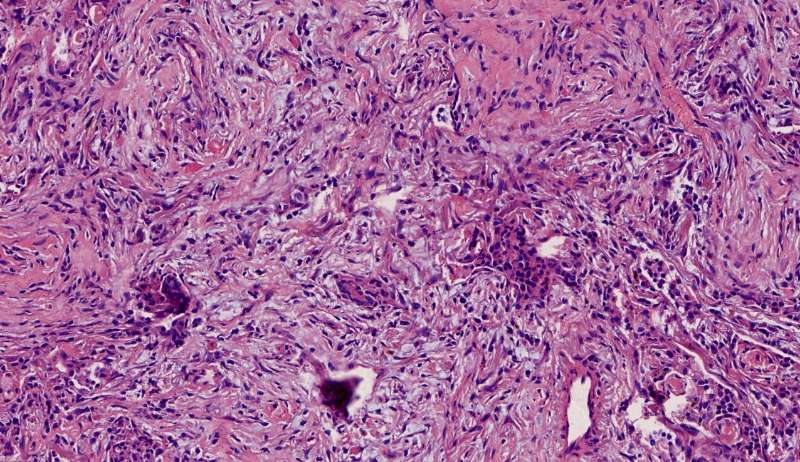

再讲讲普通慢性炎症结节

通常有机化

这是个普通慢性炎症结节,有机化(纤维增生团)